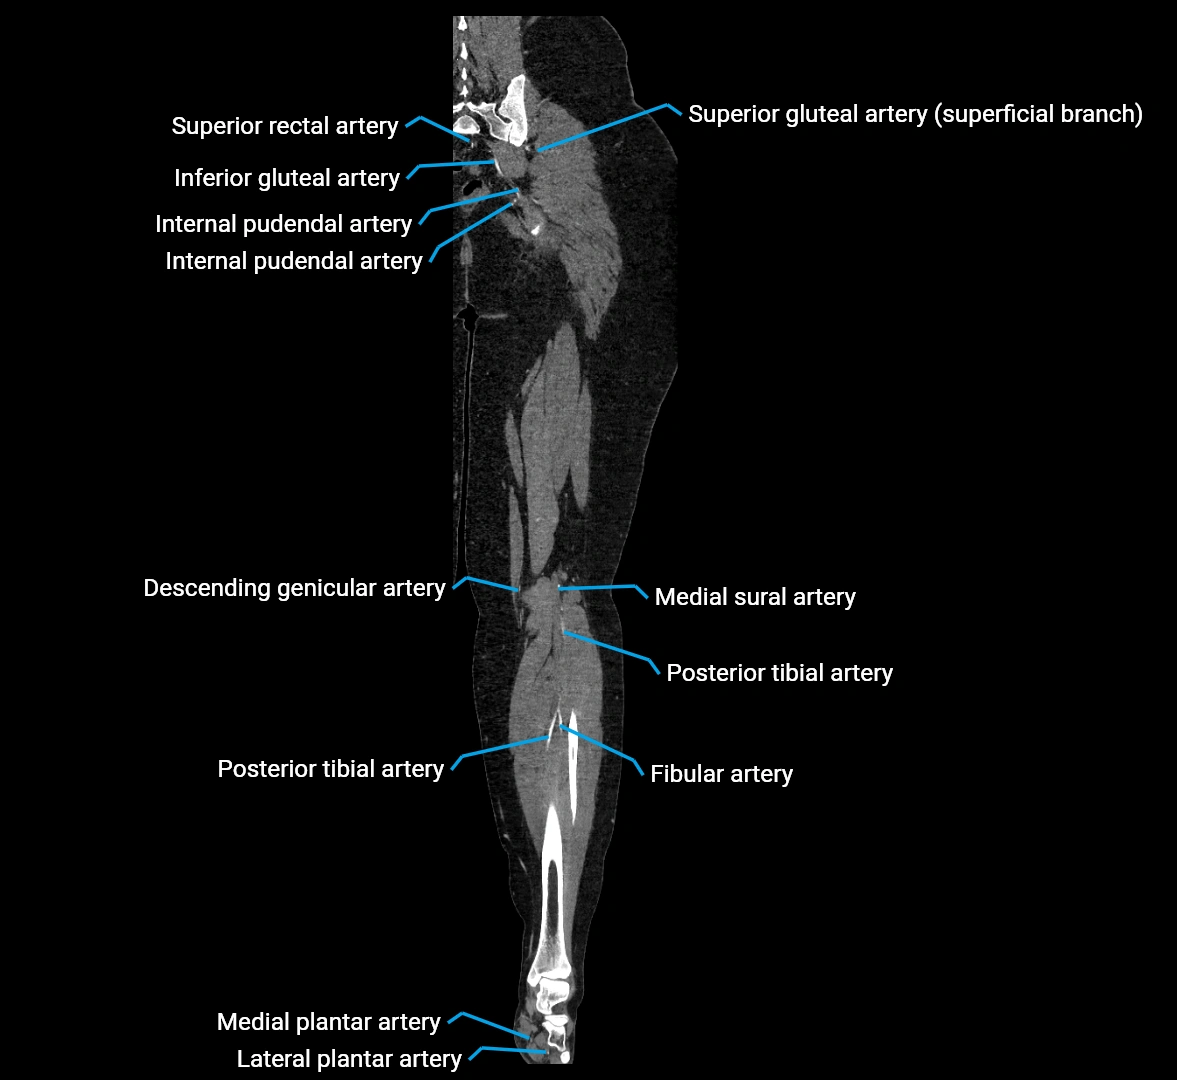

CT images

image

CT Appearance

Contrast-enhanced CT (CTA):

• Gold standard for abdominal aortic imaging

• Provides excellent detail of lumen, wall, aneurysm, thrombus, and branch vessels

• Multiplanar and 3D reconstructions help in aneurysm measurement, stent graft planning, and dissection evaluation

• Detects acute rupture, traumatic injury, or occlusion with high sensitivity